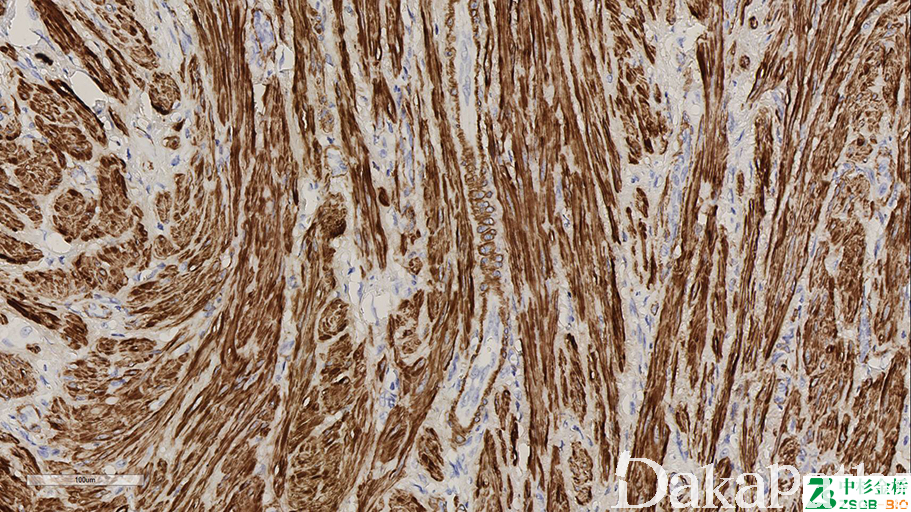

SMA

标记平滑肌及肌上皮、肌纤维母细胞来源的良、恶性肿瘤

信号定位: 胞浆